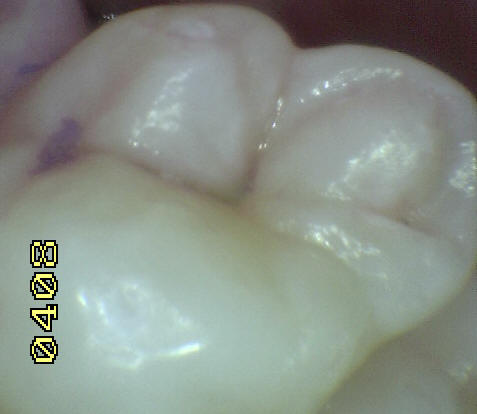

Una morfología de la fisura estrecha, con forma de botella de "Coca-Cola" genera un nicho ecológico ideal para la colonización de cualquier bacteria productora de ácidos. Al no poder remover en forma períodica dicho biofilm de una zona tan estrecha, el ataque ácido genera una lesión cariosa en la dentina, con un aspecto de esmalte intacto a la inspección visual, o sea un típico código 3 y 4 de ICDAS Completo. (Caries Moderada para el ICDAS COMBINADO)

Imagen digital que representa la microfiltración y penetración del sellante realizado.

Microfotografía: Muestra como el sellador obtura la caries subyascente, evitando su avance.

Código 3 (Caries moderada) in vitro. Los códigos 3 in vivo debe ser sellado para evitar el avance del proceso carioso. (MNO)

Código 4 (Caries moderada) in vitro. Los códigos 4 in vivo deben ser tratados en forma operatoria con preservación dental (MOPD), porque presentan dentina infectada.